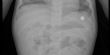

انقاذ حياة رضيعتين من الشمال ابتلعتا بطاريتين

الخميس 20/08/2015 17:15ونجح الطاقم الطبي في المستشفى بإنقاذ حياة الطفلتين , وذلك عن طريق اخراج البطارية بشكل دقيق دون التسبب بأضرار داخلية ، بح...

بعد دقائق معدودات وصل الطاقم وبدأ بتنفيذ عملية انعاش للطفلة ومن ثم تم تحويلها الى مستشفى رمبام في حيفا